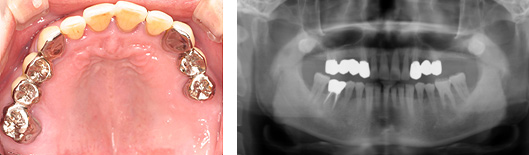

県北から来院している患者さん、55歳男性の方です。上の両方奥歯が腫れて痛んで何にも噛めず、地元の歯医者さんに診てもらったら、「上の歯は歯周病が進んでいるのでいずれ全部抜歯して総入れ歯の治療しかない。インプラントも骨がないのでできない」といわれたそうです。

歯周病がかなり進んでいますが、歯周病初期治療をしっかりおこない、「入れ歯は絶対嫌だ」とうい強い希望により、上顎前歯はブリッジ治療をおこない、奥歯はインプラント治療の治療計画です。

昨日は右下奥歯にインプラント埋入をおこない、上顎は去年、両方の奥歯を同日にサイナスリフトをおこない、同時にインプラント埋入をおこないました。

上顎両側同時にサイナスリフトをおこない、同時にインプラント埋入をおこないました。